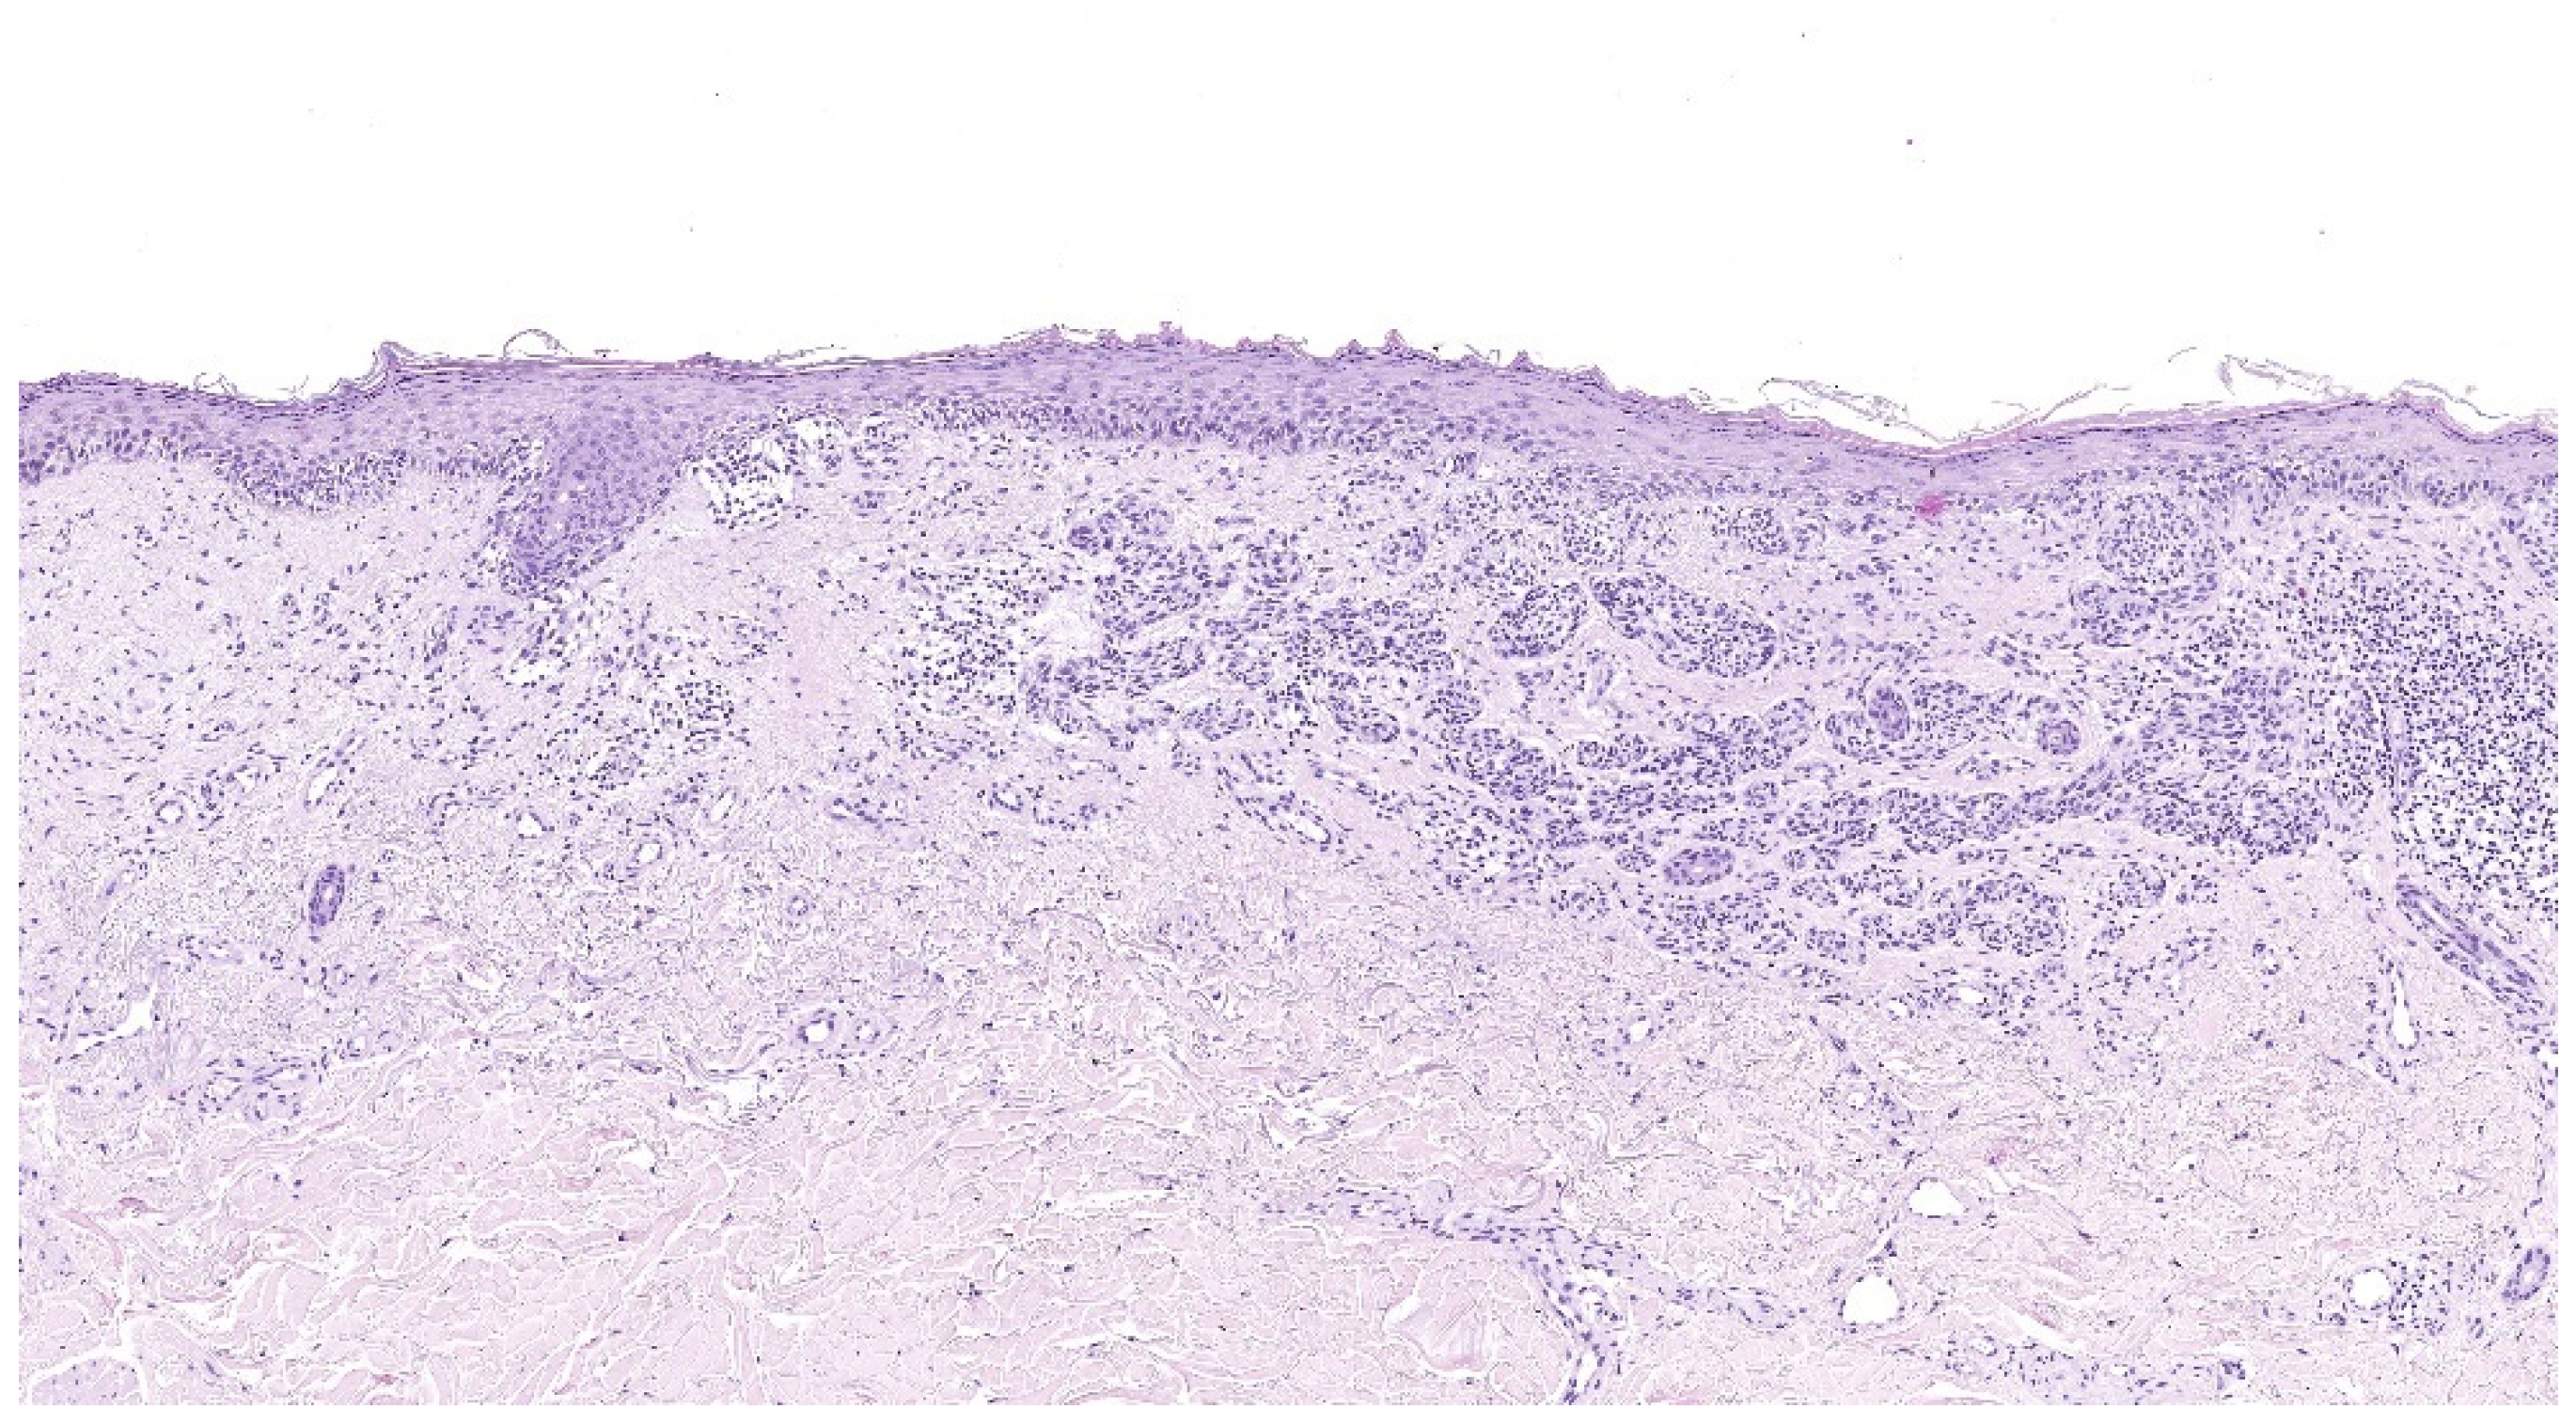

4.1. Superficial Spreading Melanoma